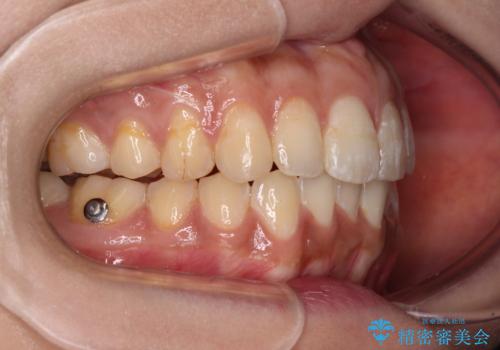

舌突出癖改善のためのトレーニングを行いながら、インビザラインにて矯正治療を行うこととしました。

舌のトレーニングをしっかりと行っていただき、上下前歯をしっかりと接触させることができました。

咬合力が強いため、治療途中に奥歯が咬み合わない期間が続きましたが、上下の奥歯でゴムかけを行っていただき、違和感なく咬み合うように仕上げることができました。